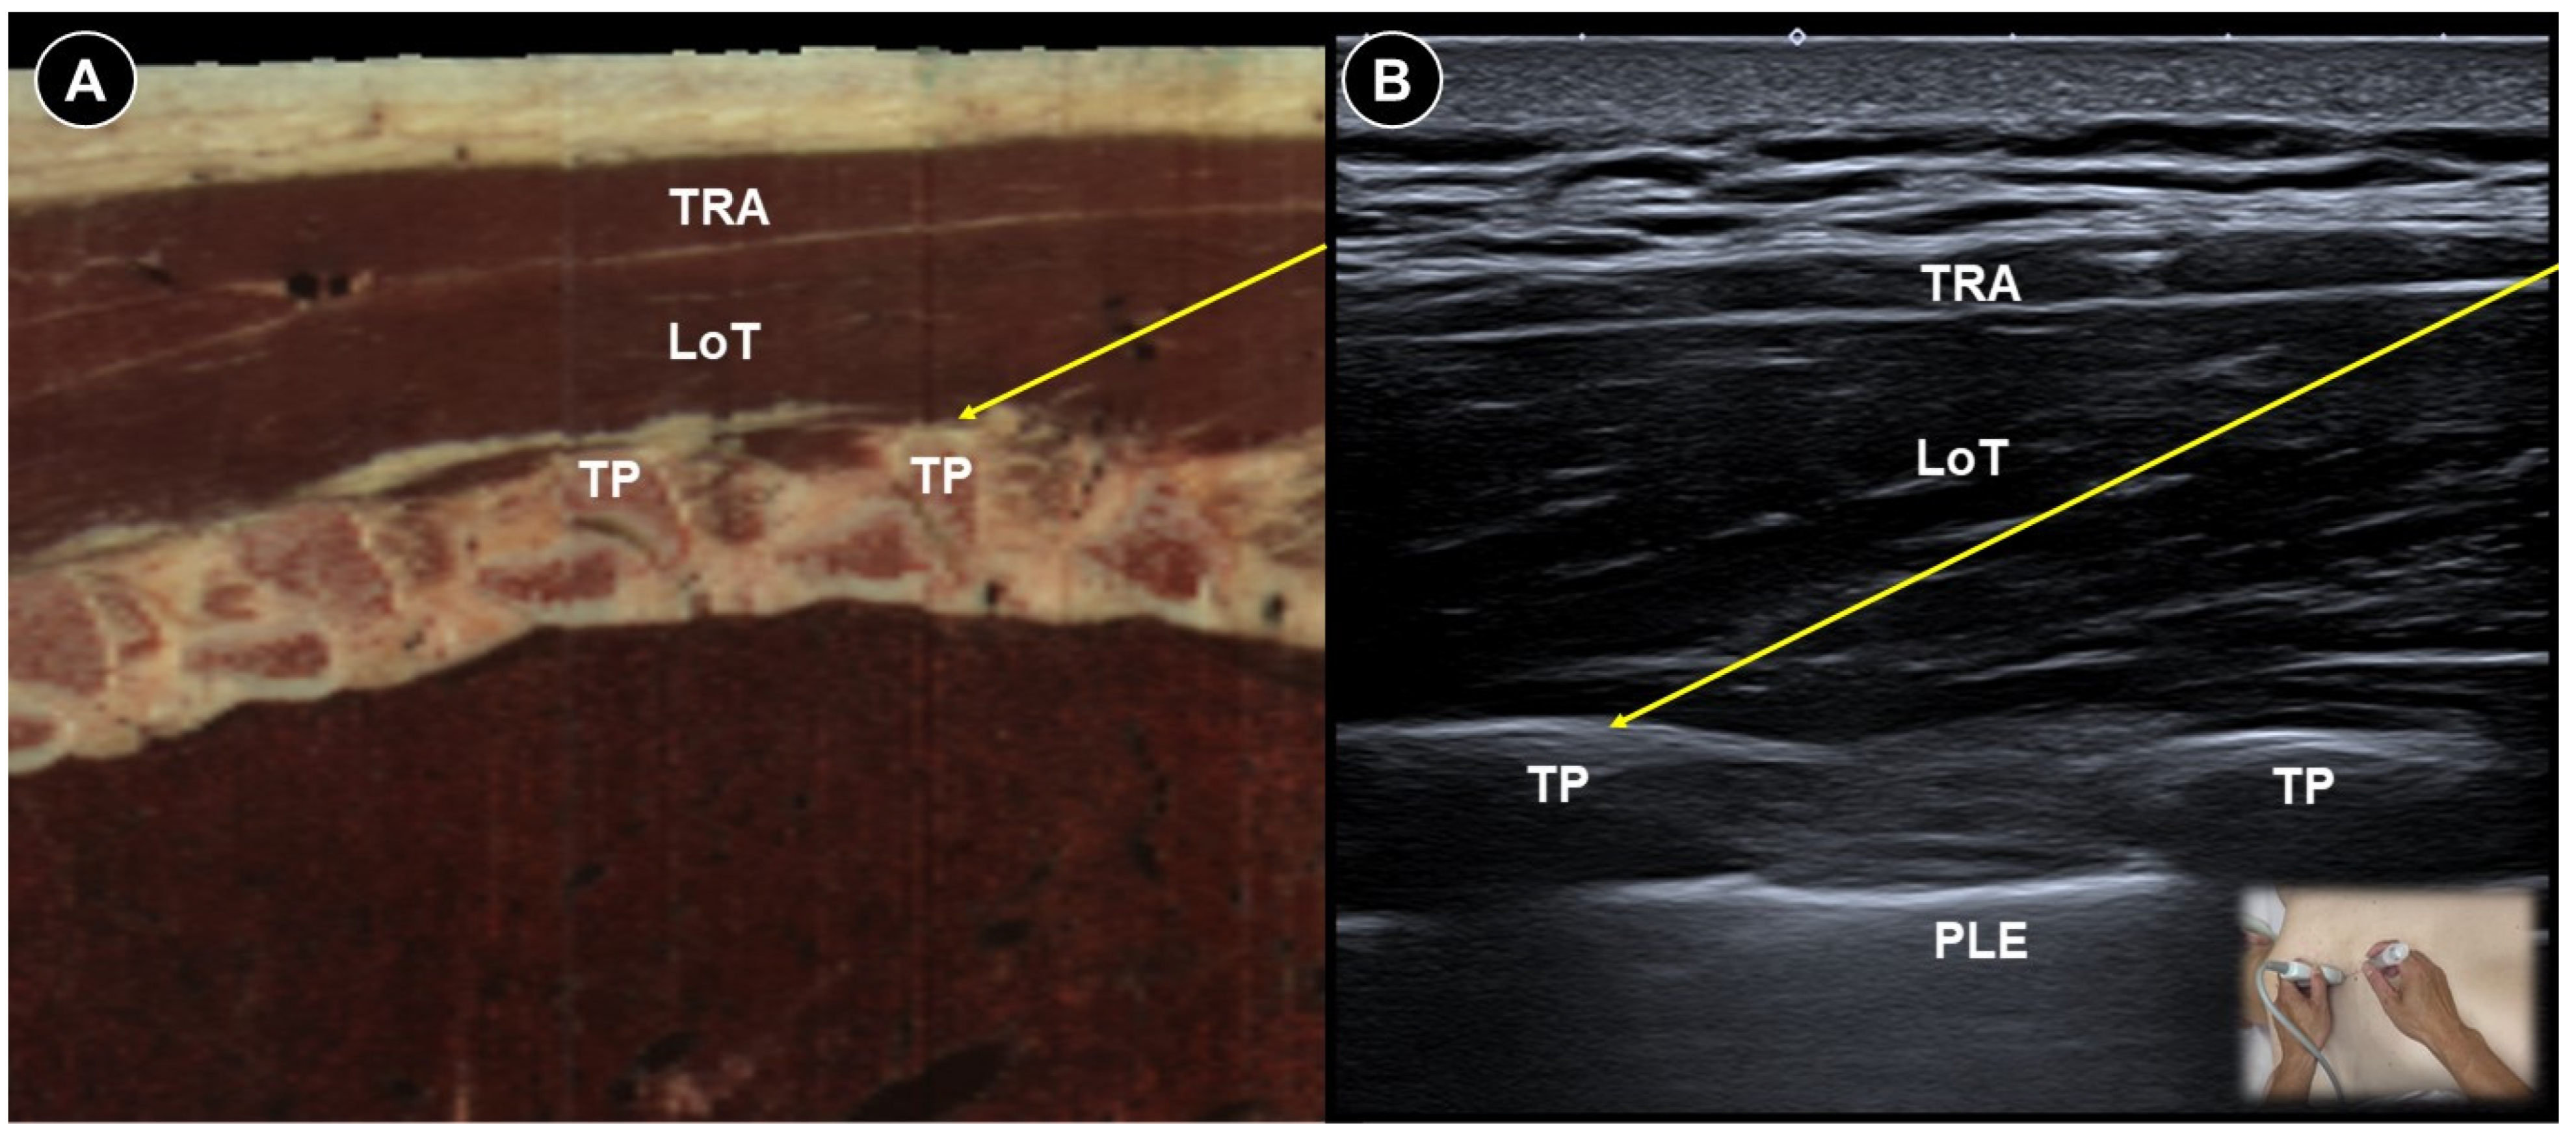

| Acute herpes pain | Burning, stabbing, or itching pain in the affected dermatomal distribution | Reactivation of VZV leading to viral nerve damage and inflammation | Cervical: supine, head turned to contralateral side Thoracic: prone | Cervical:

| Reduce pain and lower postherpetic neuralgia incidence by TPVB/ESPB (meta-analysis), PRF/SNRB/SGB (RCT) |

|

| Post-herpetic neuralgia | Persistent pain after rash resolution | Central and peripheral sensitization | Effective pain control by PRF (RCT), TPVB/SNRB/brachial plexus block/SGB/PNS (case study) | |||

| Painful radiculopathy | Pain, numbness, clumsiness and even weakness in the distribution of the affected nerve root | Mechanical compression and inflammatory irritation of the nerve root, often due to disc herniation or spondylosis | Cervical: supine, head turned to contralateral side Lumbar: prone | Cervical: linear, in-plane

| Improvement of pain by ESI (meta-analysis), SNRB/caudal block (RCT) |